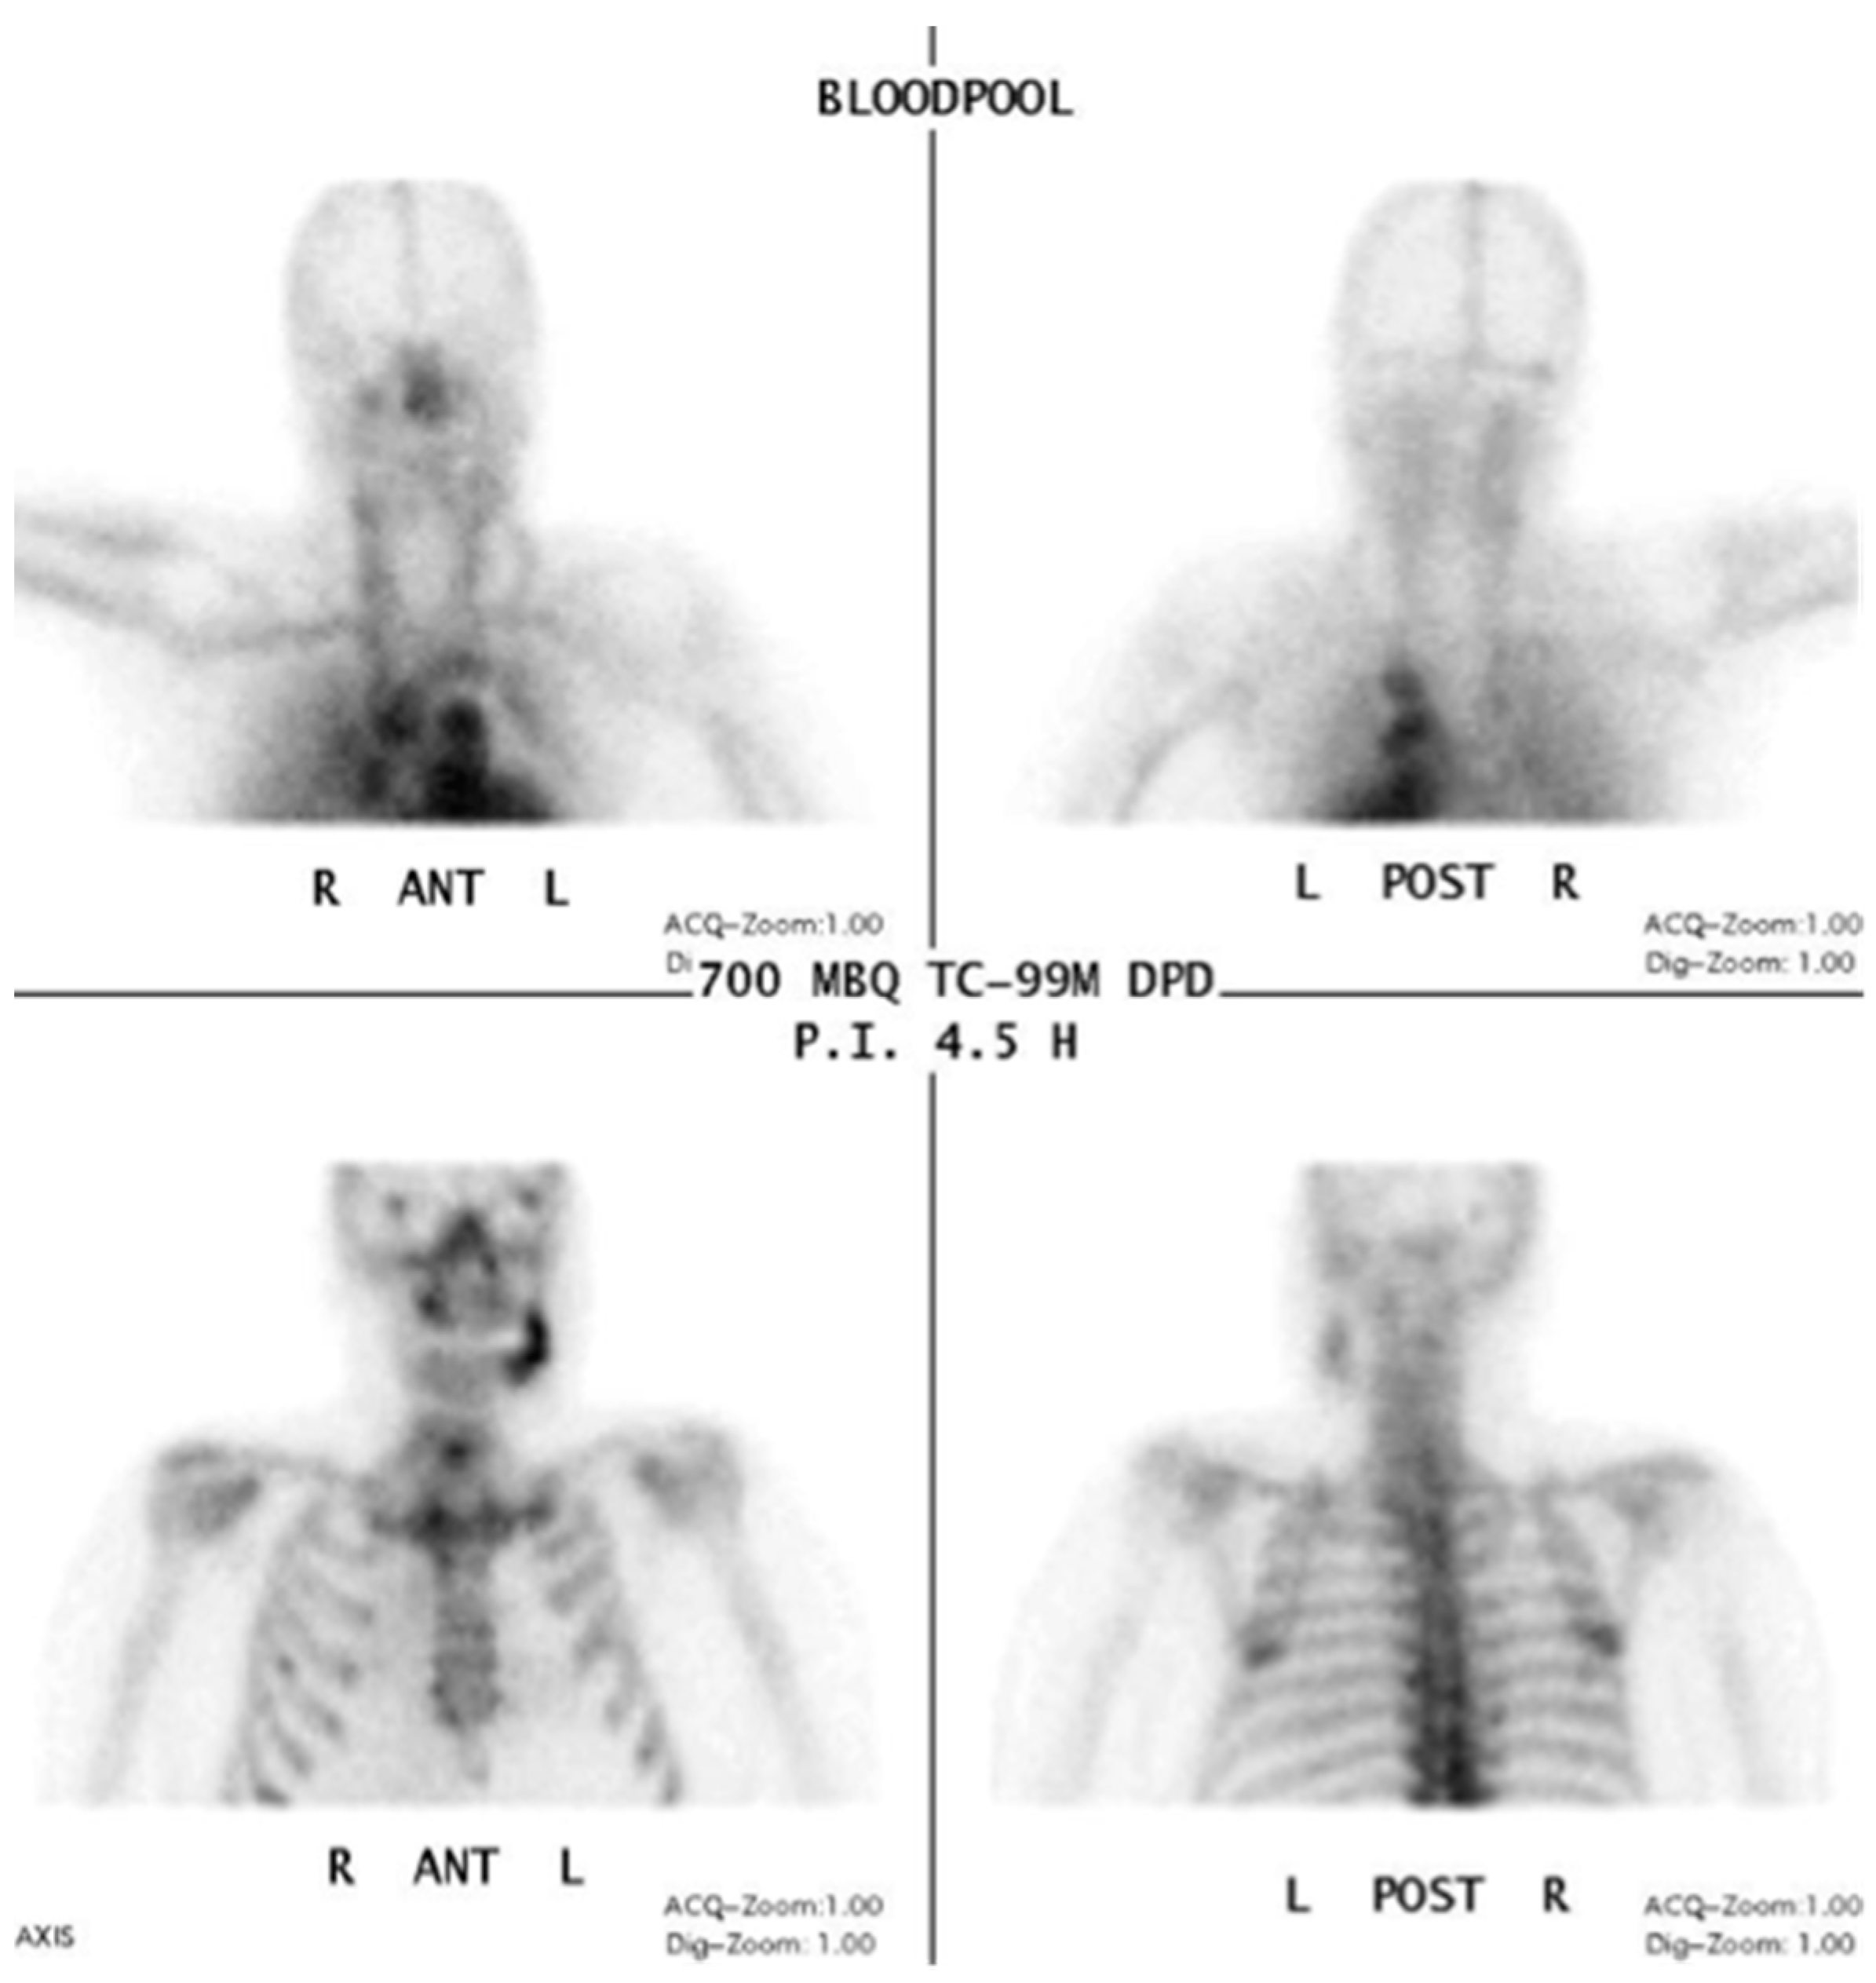

In functional imaging of bone diseases, a skeletal scintigraphy is one of the basic imaging modalities (“bone scan”). In a case analysis by Chiu et al. 10 out of 13 patients showed focal abnormal activity (increased radionuclide uptake with central decrease) in scintigraphy imaging [46].

Information from a planar scintigraphy is displayed in a two-dimensional form in contrast to SPECT. An example of technetium-99m-3,3-diphosphono-1,2-propanodicarboxylicacid (99Tcm-DPD) SPECT and 99Tcm-DPD SPECT/CT is seen in Figure 8 and Figure 9 respectively.

Figure 8.

Planar scintigraphy (Siemens, Symbia) Blood pool phase. Patient: 66 years old, male, secondary osteoporosis due to castration, alendronate. AAMOS staging: stage 3.

In SPECT imaging, the distribution of the radionuclide is monitored in multiple two-dimensional images and from multiple angles. From these datasets, a three-dimensional image is then calculated. If anatomical imaging should be added, hybrid SPECT/CT scanners are available. For detecting bony infections, technetium-99m methylene diphosphonate (99Tcm-MDP) or technetium-99 m-DPD (99Tcm-DPD) are frequently used nuclides; they show no significant differences in detecting “pathologically increased bone uptake” [47]. MRONJ should not show an uptake in the necrotic zone, but due to the associated infection, a nuclide uptake may be seen. O’Ryan et al. [48] published a retrospective study on MRONJ patients who had received whole-body planar bone scintigraphy. They used the following scoring system for the jaw: “score 0, no visual evidence of increased uptake was present; score 1, uptake was mild and equal to that in the sternum; and score 2, uptake was intense and greater than that in the sternum” [48]. The comparison with the sternum uptake was based on a paper published by Kakhki et al. [49]. Kakhki et al.’s paper, a study on 334 patients who had no diseases of the sternum/chest wall or malignancy, assessed the normal uptake in a sternum considering the age of the patient [49]. O’Ryan et al. found a nuclide uptake in 65.7% of their MRONJ patients. From their point of view, scintigraphy might have a prognostic value and physicians should watch out for newly occurring uptake in the jaws [48]. Thomas et al. assessed the impact of bone scintigraphy in patients with metastatic castration-resistant prostate cancer who had received bisphosphonates. Their focus was on early prediction of clinically asymptomatic MRONJ. MRONJ was significantly more often developed in patients with a pathological tracer uptake [50]. Ristow et al. investigated the bone turnover in the jaw of breast cancer patients who had received no antiresorptive medication, bisphosphonates, or denosumab. Interestingly, they found that “there was similar turnover of bone in the mandible compared with other skeletal sites (such as the femur), while the maxilla showed significantly higher turnover”. Since the majority of MRONJ lesions occur in the mandible, the bone turnover role of the MRONJ pathogenesis must be further reviewed [51].